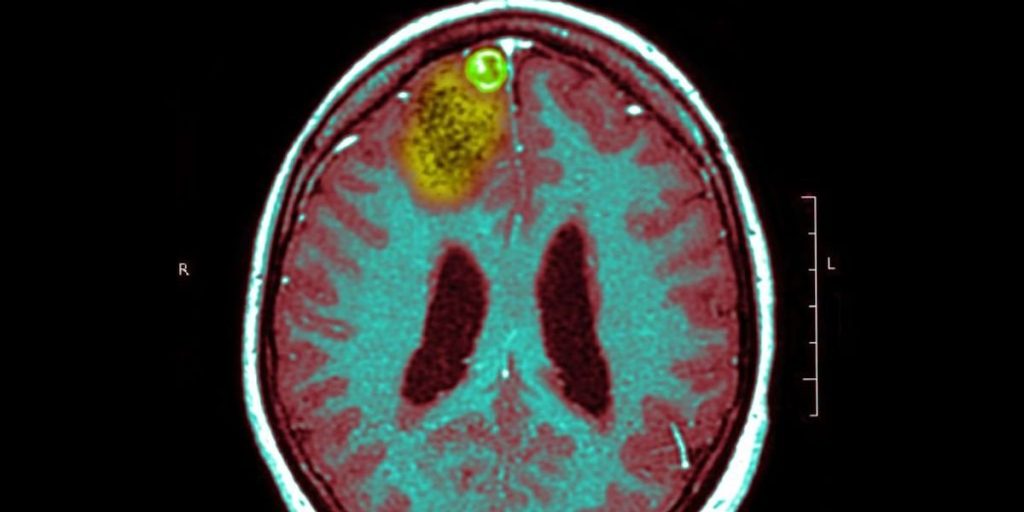

Doctor tries experimental cancer treatment to cure glioblastoma from a brain tumor

A leading skin cancer doctor is holding out hope that an experimental treatment could work miracles and cure a nearly incurable brain tumor. Richard Scolier is a professor and surgical pathologist at the University of Sydney, Australia. Professor Scoria also suffers from glioblastoma, one of the most deadly cancers. of mayo clinic Glioblastoma is defined […]